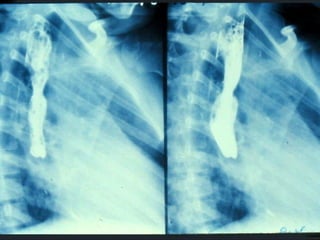

SEGD PATOLOGÍA  ESOFÁGICA A.- Estrechamientos y dilataciones secundarias Acalasia Estenosis Esclerodermia Enf. de Chagas Neoplasia Lesiones por quemadura (cáusticos y dietéticos etc.)

SEGD PATOLOGÍA ESOFÁGICA C.- Perforación Esofágica. Frecuentes: Dilataciones   Endoscopia 75% (Cricofaringea) Raras:    Síndrome Zollinger Ellison   Heridas penetrantes   CA. De Esófago.

SEGD PATOLOGÌA ESOFÀGICA D.- INFLAMACIÓN: Esofagitis péptica por reflujo Esofagitis por radiación Esofagitis medicamentosa Esofagitis cáustica

SEGD PATOLOGÍA ESOFÁGICAC.- Perforación Esofágica. Frecuentes: Dilataciones Endoscopia 75% (Cricofaringea) Raras: Síndrome Zollinger Ellison Heridas penetrantes CA. De Esófago.

SEGD PATOLOGÌA ESOFÀGICAD.- INFLAMACIÓN: Esofagitis péptica por reflujo Esofagitis por radiación Esofagitis medicamentosa Esofagitis cáustica